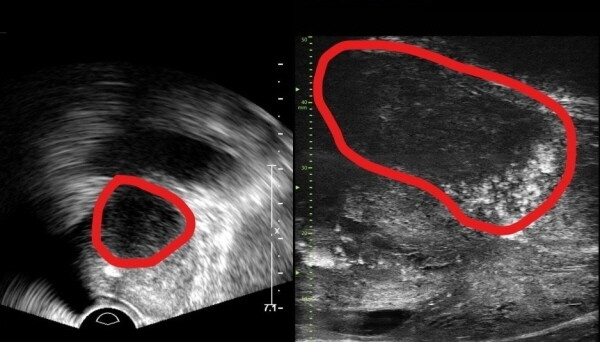

| ▲ 기존 전립선 초음파 사진(좌) 및 마이크로 초음파 사진(우). 기존 초음파는 전립선 부위(동그라미 친 부분)의 음영 차이로만 병변을 확인했지만, 마이크로 초음파는 높은 해상도를 통해 종양과 주변 조직의 모양까지 확인할 수 있다. (사진= 분당서울대병원 제공) |

기존의 경직장 초음파는 낮은 해상도로 인해 작은 전립선암 병변을 감지하는 데 한계가 있었다. 그러나 마이크로 초음파의 고해상도와 실시간 영상 구현 능력은 자기공명영상(MRI)으로도 발견하기 어려운 전립선암을 진단하는 데에도 크게 기여할 것으로 전망된다. 이는 MRI 검사에 비해 환자에게 가해지는 신체적, 심리적, 경제적 부담을 줄일 수 있다는 장점도 가진다.